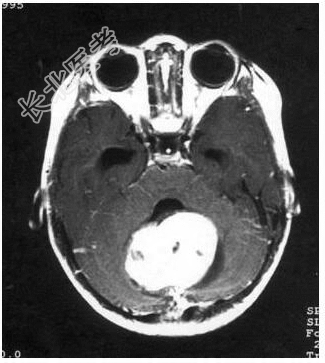

病历摘要:患儿男性,11岁。半年前开始出现行走不稳,常无故跌倒。半月前出现发作性剧烈头痛,伴恶心呕吐。体检:T36℃,P100次/分,R22次/分,BP100/60mmHg,神清,言语较缓慢,双眼外展约不及边,双眼侧视时有小幅度水平眼震。四肢肌力正常,右上肢肌张力较低,坐位姿势不稳,常不自主摇晃,双上肢指鼻不准,行走蹒跚步态,足距扩大,身前倾。患儿行头颅MR检查(见图)